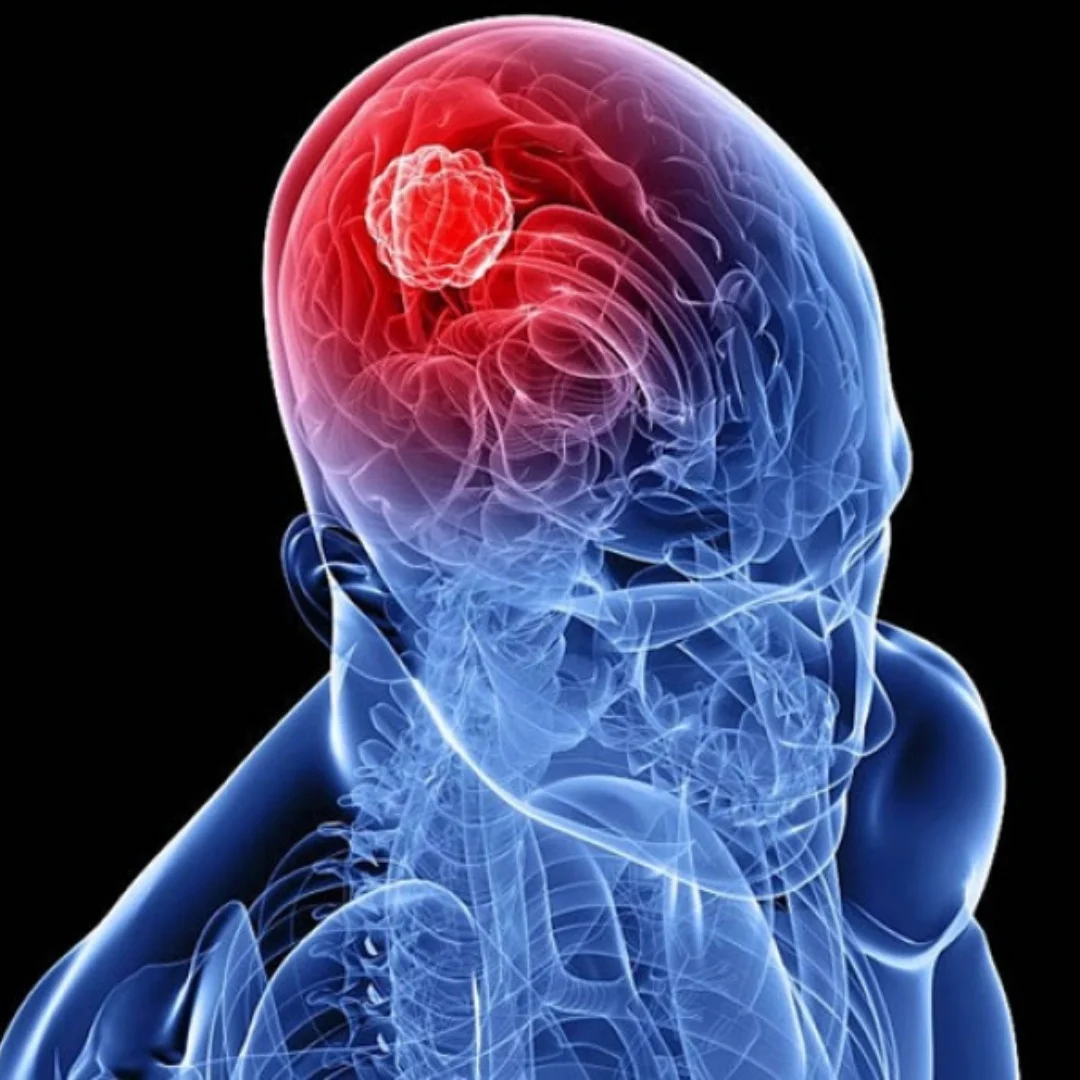

- Accidente Cerebro-Vascular (ACV)

Accidente Cerebro-Vascular (ACV)

La terapia busca reparar el tejido cerebral dañado tras un evento isquémico o hemorrágico, promoviendo la creación de nuevos vasos sanguíneos y conexiones neuronales para mejorar la recuperación motora.